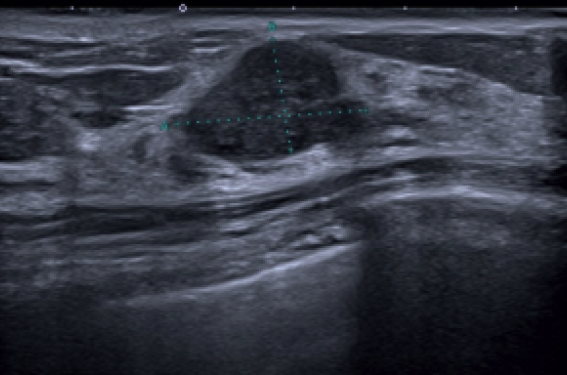

En 2021, une patiente de 42 ans sans facteur de risque consulte pour masse palpable apparue du QSI droit. Elle a pour antécédent l’exérèse d’un adénofibrome en 2004 à gauche. La masse palpable est visible en mammographie et en échographie (figures 1 et 2), classée 4 b dans notre centre. La biopsie est réalisée dans un autre cabinet. L’ana-pathologie, non vue, hésite entre phyllode et adénofibrome. Une IRM complémentaire est donc de nouveau réalisée dans notre centre. La masse se rehausse ainsi que plusieurs formations bilatérales à contrôler à 6 mois (figure 3). La patiente est opérée de la masse, un adénofibrome finalement (ana-pathologie non vue), mais ne contrôle pas par une IRM comme demandé.

Figure 1. Adénofibrome de contoursirréguliers en 2021, opéré, doute sur une phyllode. Figure 2. Mammographie de 2021, sein dense, masse palpable du qSI, qui sera opérée. Figure 3. IRM en 2021, rehaussements de la masse palpable du QSI et bilatéraux à recontrôler. En octobre 2023, elle se présente...